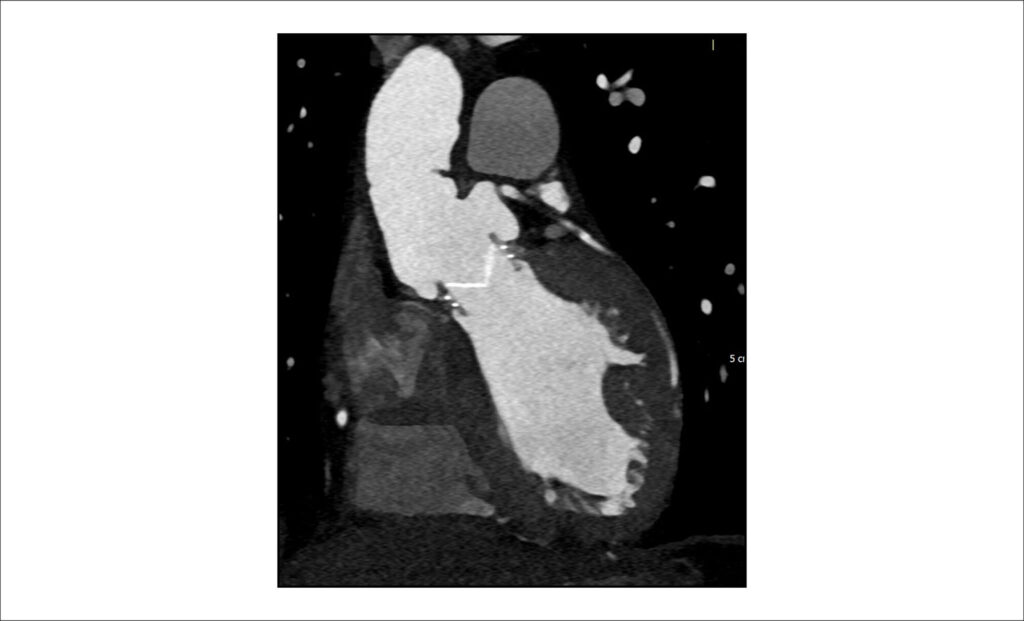

A Angiotomografia Computadorizada (ATC) tem sido um recurso importante no diagnóstico cardiovascular há décadas. A melhoria contínua na aquisição rápida de dados, frequentemente com resolução espacial mais alta, consolidou o método como indispensável para o diagnóstico e manejo de diversas condições cardiovasculares, como aneurismas, dissecção aórtica e tromboembolismo pulmonar., O uso da ATC na imagem cardíaca e coronariana também conquistou território e relevância importantes., As técnicas de Tomografia Computadorizada (TC) vêm avançando significativamente desde sua introdução na medicina. Desde os detectores únicos, passando pelos tomógrafos helicoidais, tomógrafos multidetectores com pitch elevado, melhorias nos algoritmos de reconstrução, surgimento da tecnologia de dupla energia e, mais recentemente, a capacidade de adquirir imagens de todo o coração em apenas um batimento cardíaco com informação de todo o ciclo cardíaco, são marcos impressionantes. A Reserva de Fluxo Fracionado por TC (do inglês, FFR-CT) também é uma técnica muito promissora. O progresso, no entanto, apresenta certas desvantagens: a radiação ionizante continua sendo uma preocupação e, apesar das estratégias de redução como a modulação de dose, alguns exames cardiovasculares de ATC ainda apresentam níveis relativamente altos de radiação absorvida, especialmente aqueles com múltiplas séries, cortes extremamente finos e reconstruções retrospectivas de porções maiores do ciclo cardíaco. Seguindo essa tendência de melhorar a qualidade da imagem com a menor radiação ionizante possível, surgiu uma nova técnica complexa: a TC com Contagem de Fótons (PCCT, da sigla em inglês).